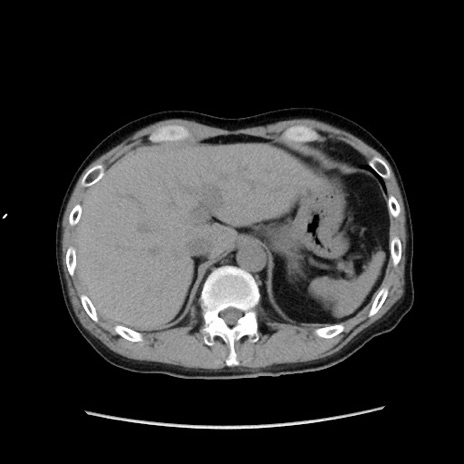

冠状断像

【症例】40歳代 男性

【主訴】腹痛

【現病歴】4時間ほど前に電車に乗車中に臍部上より腹痛出現。徐々に増悪し起立困難となり、救急外来受診。生ものは数日食べていない。今朝お雑煮を食べた。

【身体所見】BT 36.8℃、BP 117/84mmHg、HR 91/min、SpO2 97%、苦悶様、腹部:臍上部広範囲圧痛あり、反跳痛±

【データ】WBC 8100、CRP 0.03